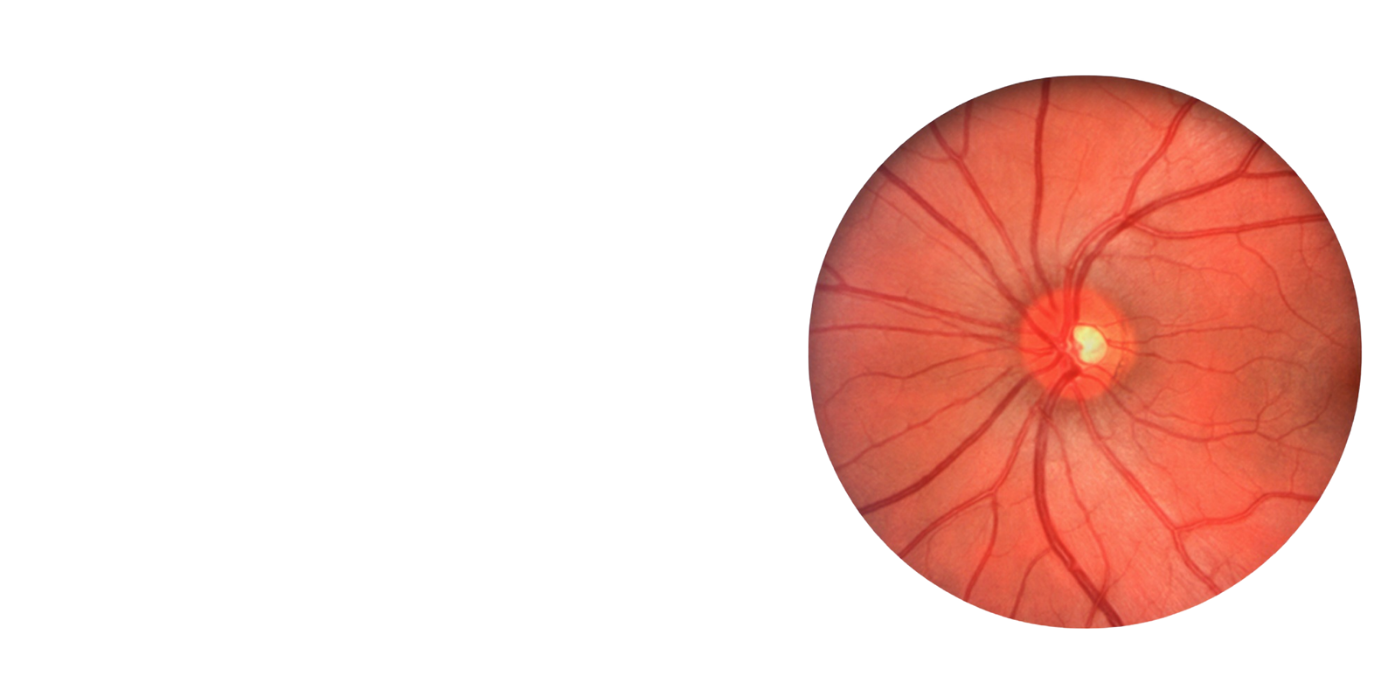

Explore our solutions for fundus imaging, from precision hardware to powerful software and seamless DICOM integration.

FDA cleared complete innovative solution for your digital imaging needs